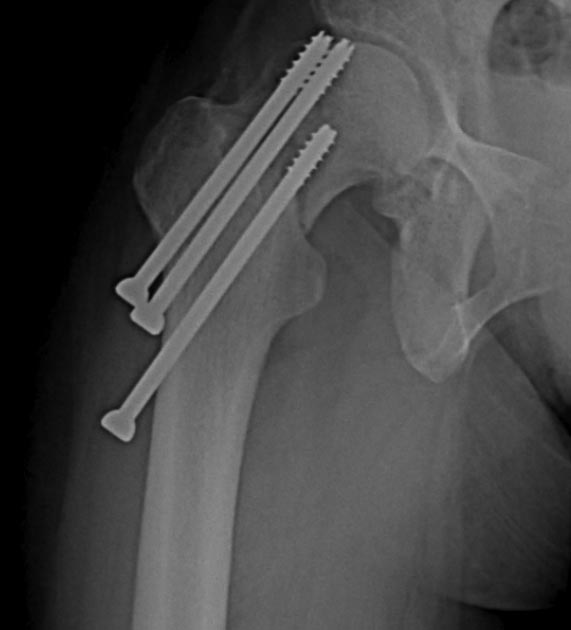

Две несросшихся шейки бедра, пацинтка 27 лет, травме 5 месяцев

Травма 5 месяцев назад кататрвма.

БИОС плеча, Чкдо на л/запястный сустав, Биос левого бедра, Мос правой шейки

бедра винтами.

Причина обращения -выявленный ложный сустав шейки левого бедра. При

дообследовании выявлен несросшийся перелом шейки бедра на винтах.

правой конечностью.Справа остесинтез с коррегирующей остеотомией, но смущает

состояние верхнего полюса после миграции винтов, что может повлечь

протезирование на фоне нарушения анатомии проксимального бедра, что не

хорошо для выживаемости протеза у 27 летней пациентки. Может сразу протез

?КТ головки не информативна из-за винтов

На шейке с шурупами понятно остеотомия и фиксатор с угловой стабильностью, а

слева надо бы определится что с головкой

, живая или нет. Я бы сделал изотопное сканирование с технецием BONE SCAN.